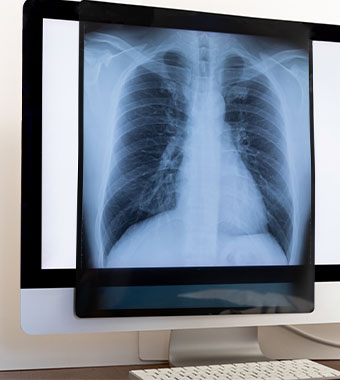

まず、医師は患者さんの症状や病歴を詳しく聞きます。咳や痰の有無、熱の高さ、息苦しさなどを確認し、聴診器を使って肺の音を聞くことで、肺に異常がないか確認します。次に、胸部X線検査が行われます。これは、肺炎の診断に最も重要な検査で、肺に炎症があるかどうかを画像で確認します。肺炎を起こしている部分は白く影となって映るため、診断の確定に役立ちます。さらに、血液検査や痰の検査を行い、炎症の程度や原因となっている病原体を特定することもあります。間質性肺炎を疑う場合には、これらに追加して呼吸機能検査を行い、検査結果を総合的に判断し、適切な治療方針が決定されます。